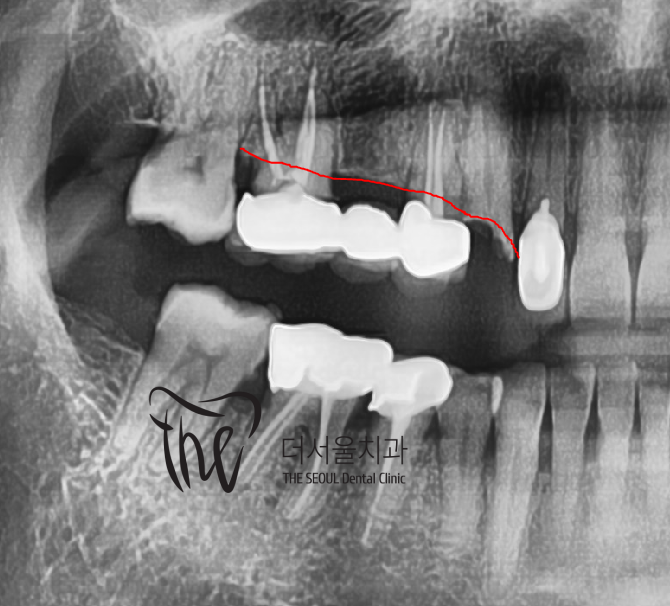

뒤쪽에 있는 브릿지 보철 또한 제거를 해야

될 거 같은 상황입니다.

이미 뼈가 너무 많이 녹았습니다.

즉, 2차 우식증도 있으면서 치조골 위축에

따라서 상태 불량입니다..

디지털 임플란트 진단을 하면서,

apical lesion(뿌리 염증) 이 있는것이 관찰이 되며

당일 발치 후 즉시식립을 하기로 했습니다.

근데.. 이미 치조골이 많이 얇죠?

전치부쪽이기 때문에

어금니 뼈 보다 더 얇습니다.ㅠㅠ